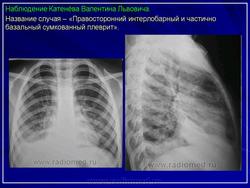

Левосторонний паракостальный осумкованный плеврит.

Правосторонний паракостальный осумкованный плеврит.